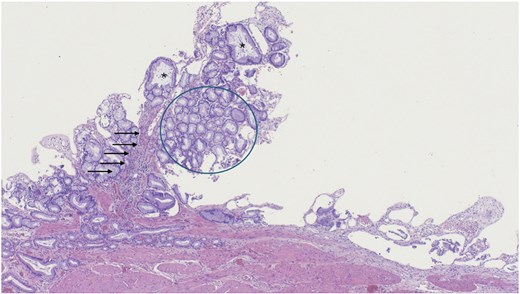

A robotic-assisted laparoscopic cholecystectomy was performed. Intraoperatively, dense omental and hepatic adhesions overlying the gallbladder complicated exposure. The gallbladder was removed in a standard fashion and sent for pathological analysis. Final pathology revealed chronic cholecystitis, cholelithiasis, and a pyloric gland adenoma. Gross examination showed a single 3.3 cm yellow–brown, crystalline ovoid gallstone, dark green velvety-to-trabeculated mucosa, and a solitary 0.2 cm polyp in the gallbladder body. The histology of the tissue specimen was reviewed by pathology which demonstrated a polypoid lesion with tightly packed pyloric type glands, consistent with PGA histopathology (Figs 2–4).

Low magnification of polypoid lesion demonstrating a fibrovascular core (arrows), and tightly packed pyloric type glands (circle) with occasional cystic dilatation (asterisk). Haematoxylin and eosin 4×.